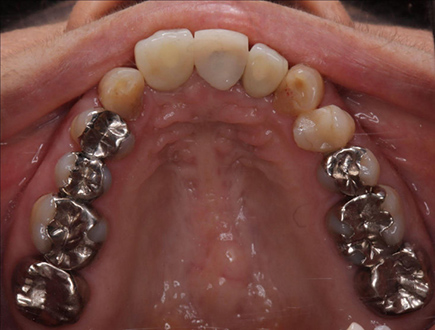

| 治療部位 | 上顎前歯部 |

|---|---|

| インプラント本数 | 4本 |

| 単価 | 40万円/本 |

| 合計費用 | 160万円 |